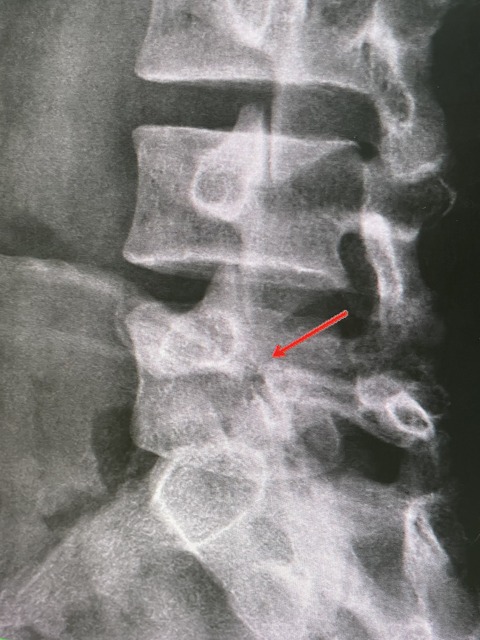

レントゲンを撮ると、強い分離症があり

現在は、分離症のサインあり、

分離症と診断し、トレーニングを開始しました